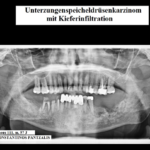

Στὴν πανοραμικὴ ἀκτινογραφία (εἰκ. 2) ποὺ διενεργήσαμε, διαπιστώθηκε, ὅ,τι τὸ πρόβλημα τοῦ ἀσθενοῦς ἔπρεπε νὰ τοποθετηθεῖ σὲ ἄλλη διάσταση, ὁπωσδήποτε πέραν κάθε ὀδοντογενοῦς αἰτίας. Ὁ ΑΡ κλάδος τῆς κάτω γνάθου παρουσιάζει πλήρη ἀποδιοργάνωση τῆς ὀστικῆς ὑφῆς του. Παρατηρεῖται διάσπαση τοῦ ὀστικοῦ φλοιοῦ, εἰκόνα δίκην μωσαϊκοῦ τῆς ὑποκείμενης σπογγώδους ὀστικῆς οὐσίας ὑπὸ τὴν ἔννοιαν ἐναλασσόμενων διαυγαστικῶν καὶ ἀκτινοσκιερῶν ἑστιῶν ἀλλόκοτου ἢ ἀκανονίστου σχήματος καὶ ποικίλλου μεγέθους-πάντως μικροῦ-. Οἱ παρατηρούμενες ἀλλοιώσεις φαίνεται νὰ ἐπεκτείνονται μέχρι τοῦ συστοίχου φατνιακοῦ πόρου ἢ καὶ νὰ τὸν ὑπερβαίνουν κατὰ τόπους. Ἡ εἰκόνα τοῦ ὀστοῦ τῆς κάτω γνάθου θέτει ζήτημα διαφοροδιαγνώσεως ὀστικῆς νεοπλασίας αὐτοχθόνου χαρακτῆρος δηλ. προερχομένης ἐξ αὐτοῦ τούτου τοῦ ὀστοῦ τῆς κάτω γνάθου ἢ προσβολῆς τοῦ τελευταίου δευτερογενῶς, κατόπιν διηθήσεώς του ἐκ πρωτογενοῦς νεοπλασίας ἐντοπιζομένης σὲ παρακείμενα ἀνατομικὰ στοιχεῖα. Ἡ ἰσχυρὴ ὑποψία μας γιὰ νεοπλασία τοῦ ΑΡ ὑπογλωσσίου σιελογόνου ἀδένος, ἐπινεμήσεως δὲ καὶ διηθήσεως τοῦ παρακειμένου ὀστοῦ τῆς κάτω γνάθου, στηριζόταν πρωτίστως στὴν διόγκωση τοῦ ἀδένος, ὅπως μᾶς φάνηκε καὶ στὴν ψηλάφηση ποὺ παράλληλα μὲ τὴν ἀκτινογραφία διενεργήσαμε.